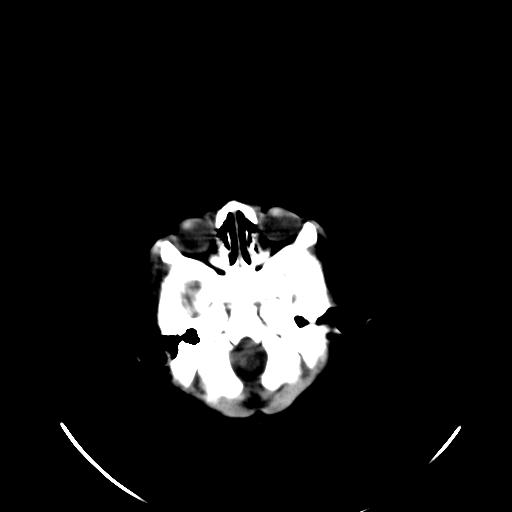

患儿 女性 1个月  今天发现阵发性抽搐  双眼上翻、凝视,嘴唇及面色青紫

双侧颞枕叶片状低密度影,考虑新生儿却血缺氧性脑病可能

新生儿却血缺氧性脑病不排除!

考虑hie。

考虑新生儿hie。